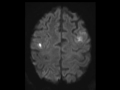

Septic Emboli

There are multiple foci of restricted diffusion that demonstrate ring enhancement, some of which additionally demonstrated a T2 hypointense rim, consistent with septic emboli in the known clinical setting of infectious endocarditis.